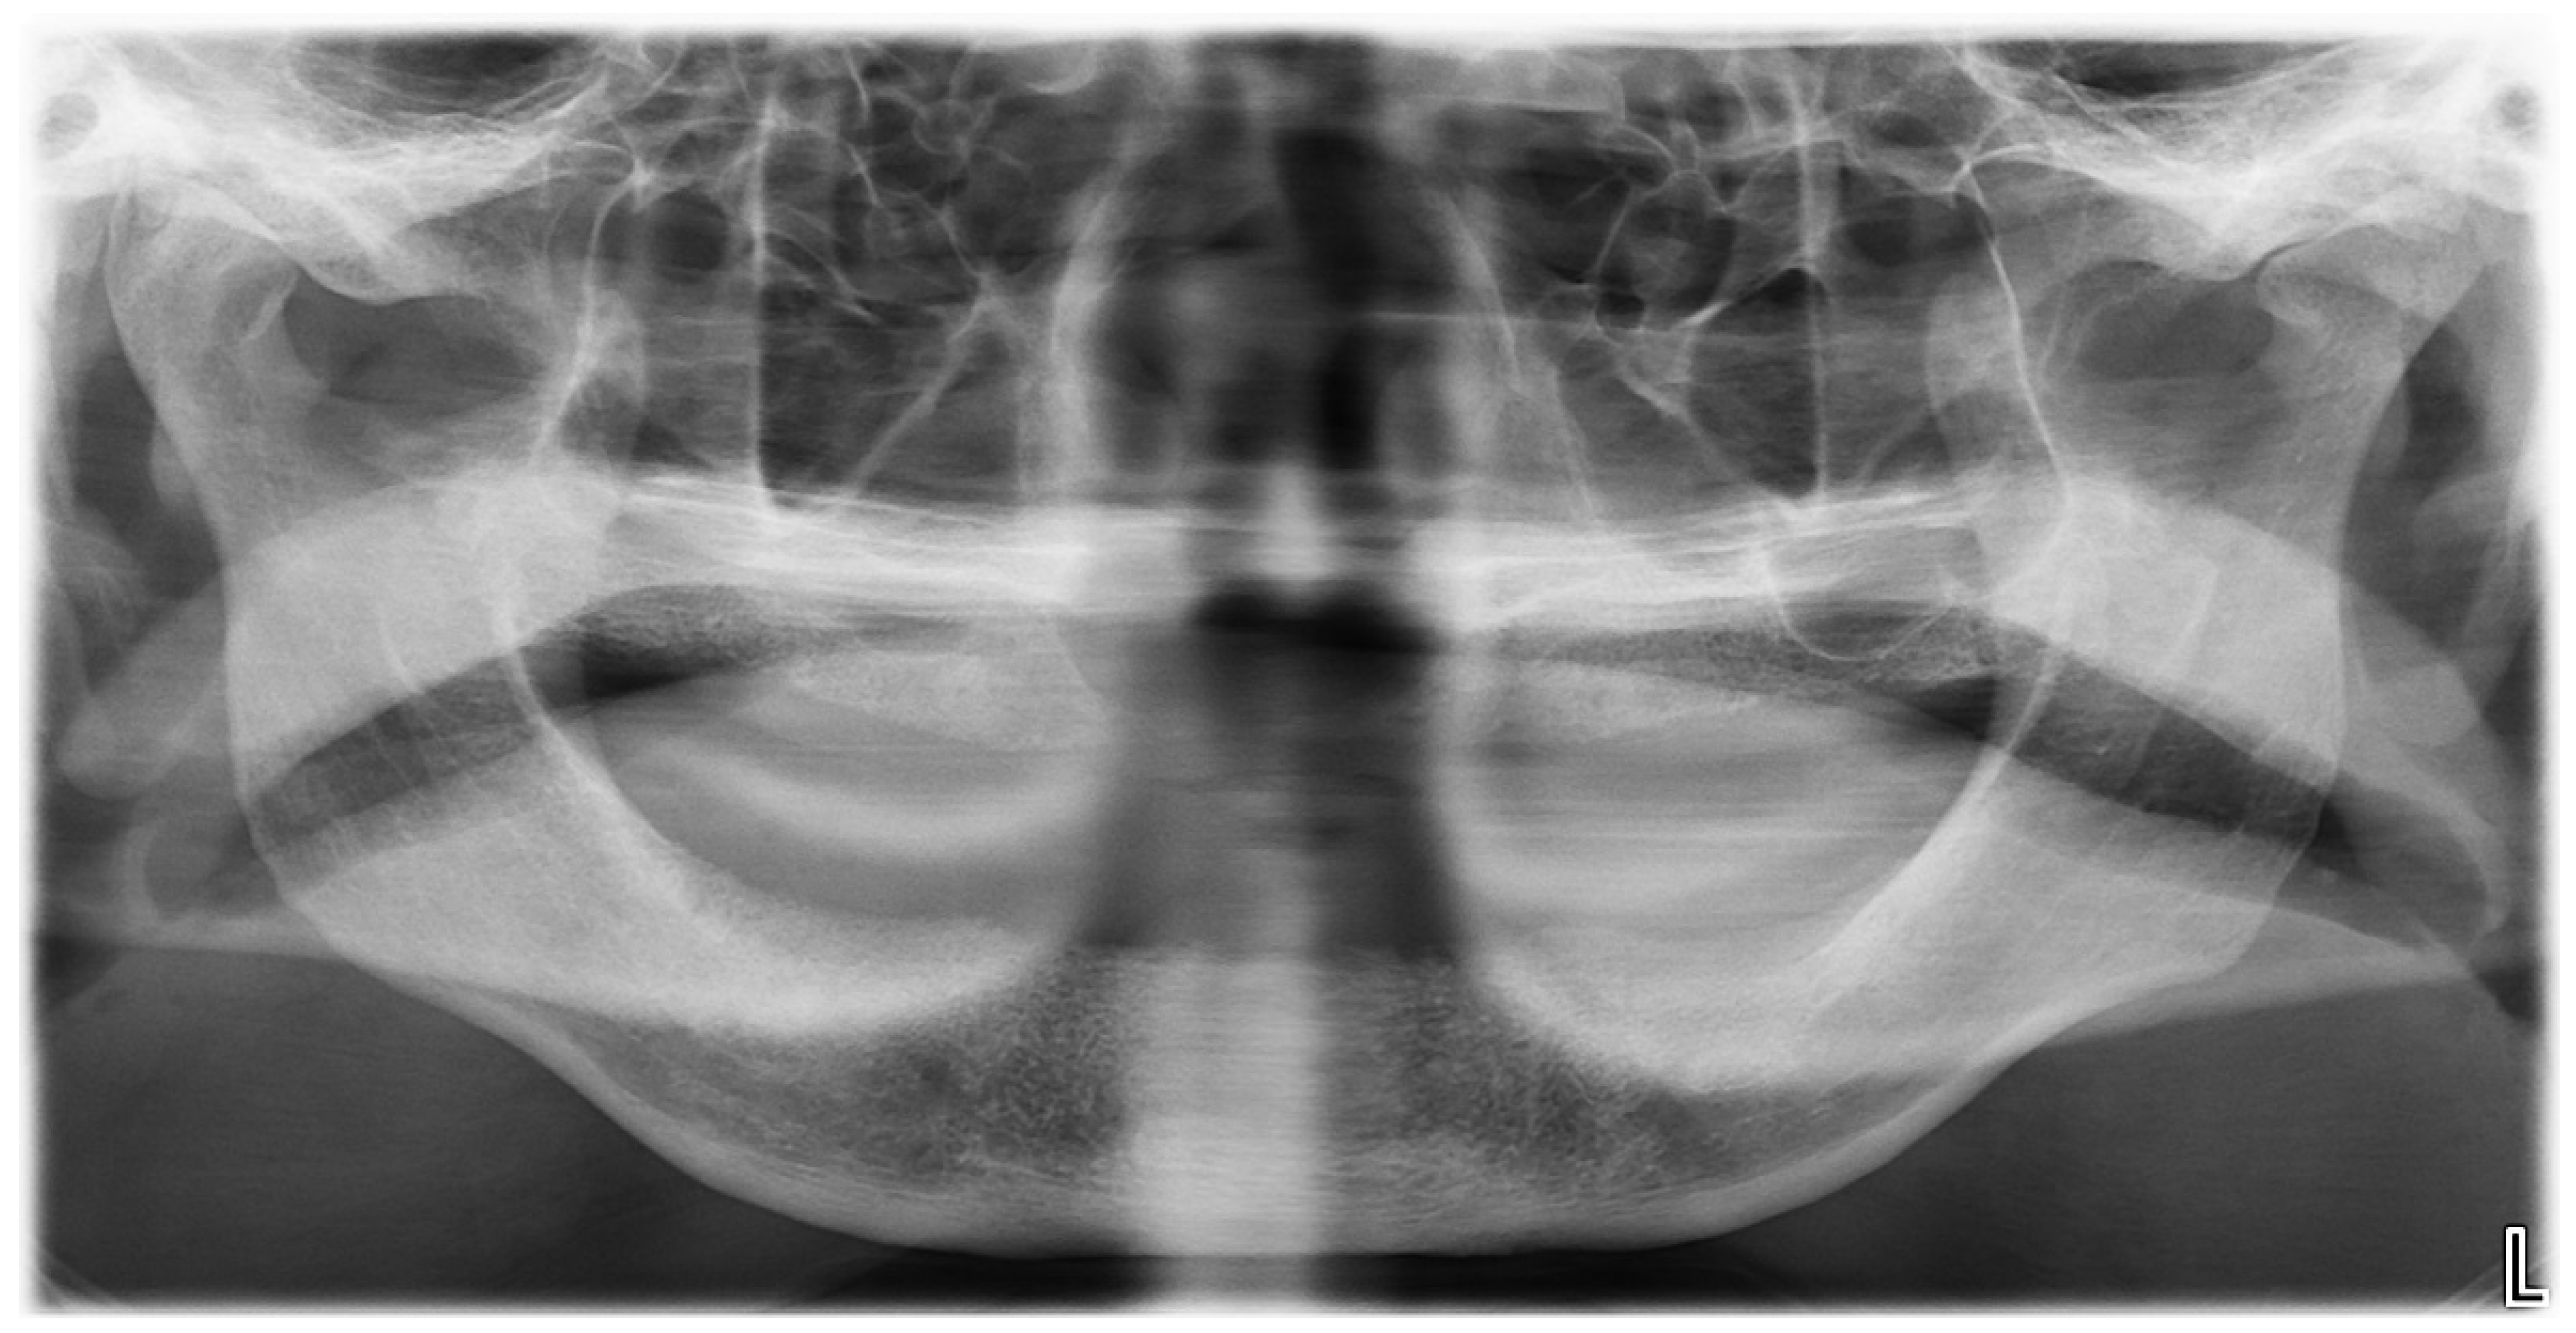

Panoramic Dental XRay of Childs Teeth Development Stock Photo Panoramic Xray Child This best practice provides guidance on the proper timing, selection, and frequency of dental radiographs for pediatric dental patients and endorses the u.s. The authors provide an in. Panoramic radiographs, an extraoral radiographic technique, is widely used in pediatric dental practice as they offer the. Panoramic radiography, particularly in the pediatric population, is rarely addressed in the radiology literature. To. Panoramic Xray Child.

Panoramic Dental Xray Child Seven 7 Stock Photo 318025592 Shutterstock Panoramic Xray Child Understanding the technical aspects of obtaining a panoramic radiograph, the relevant anatomy depicted on radiographs in. Panoramic radiography, particularly in the pediatric population, is rarely addressed in the radiology literature. This article is intended to assist the general radiologist in competently and confidently evaluating the pediatric panoramic radiograph. This best practice provides guidance on the proper timing, selection, and frequency. Panoramic Xray Child.

Panoramic Dental Xray Of A Child, Deciduous Milk Teeth Growing From Panoramic Xray Child Panoramic radiographs, an extraoral radiographic technique, is widely used in pediatric dental practice as they offer the. To (1) determine adherence to guidelines when prescribing panoramic radiographs (pr) for patients 18 y.o. This best practice provides guidance on the proper timing, selection, and frequency of dental radiographs for pediatric dental patients and endorses the u.s. This article is intended to. Panoramic Xray Child.

Panoramic Xray of the jaw. Xray of the teeth of a 12yearold girl Panoramic Xray Child The authors provide an in. To (1) determine adherence to guidelines when prescribing panoramic radiographs (pr) for patients 18 y.o. Panoramic radiographs, an extraoral radiographic technique, is widely used in pediatric dental practice as they offer the. Understanding the technical aspects of obtaining a panoramic radiograph, the relevant anatomy depicted on radiographs in. This article is intended to assist the. Panoramic Xray Child.